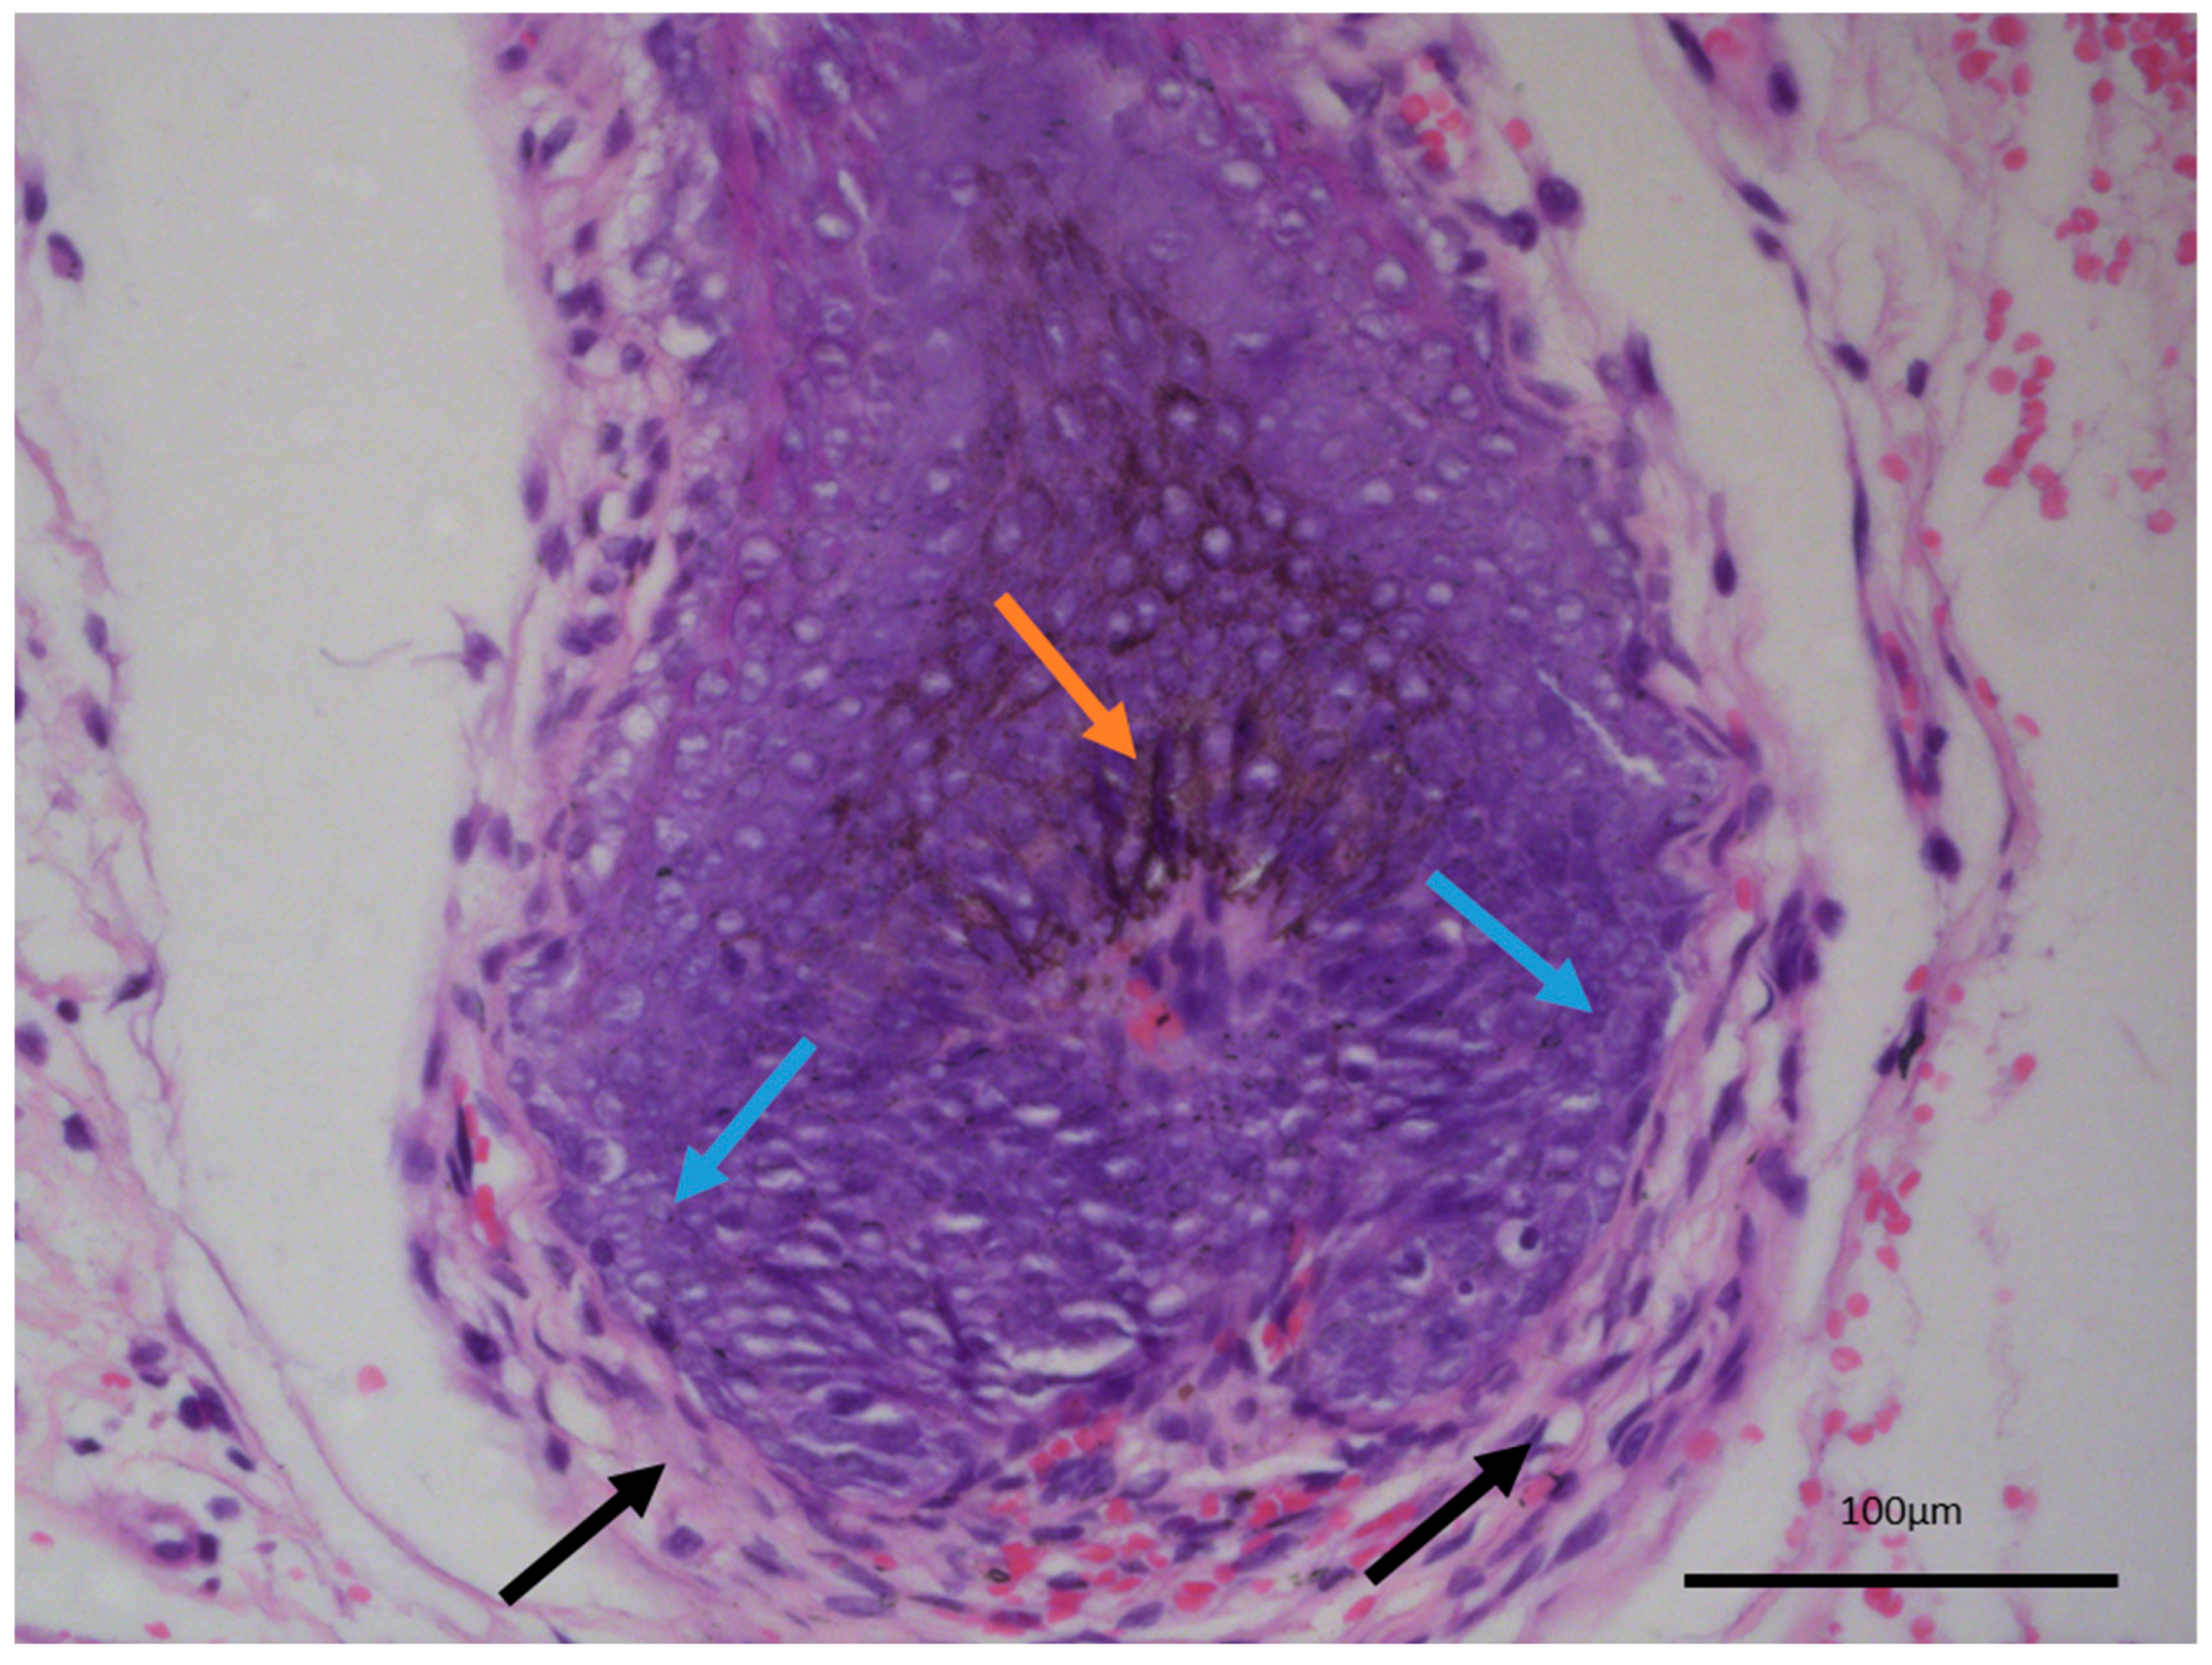

The last differential diagnosis of melanotrichoblastoma, due to its prominent pigment cell component, is that of melanoma [14,15]. While there is a melanocytic component within the tumor, both based on morphology and their immunophenotype characteristic, these are completely benign cells within the tumor, recapitulating the naturally occurring dendritic melanocytes of the hair follicles, which give out their melanin pigment to the hair shaft and color the hair. As such, melanotrichoblastomas not only represent a benign tumor, but can be viewed as the best differentiated variety of trichoblastoma as they completely reenact the structure of the hair follicle—epithelial, mesenchymal, and melanocytic components—with only the growth pattern differing from a normal hair follicle (Figure 4).

Figure 4.

Normal hair follicle histology, internal control from adjacent non-involved tissues from the same patient. Dendritic melanocytes (orange arrow), palisading epithelial cells (blue arrows), and hypercellular wrapping stroma (black arrows), original magnification 200×.